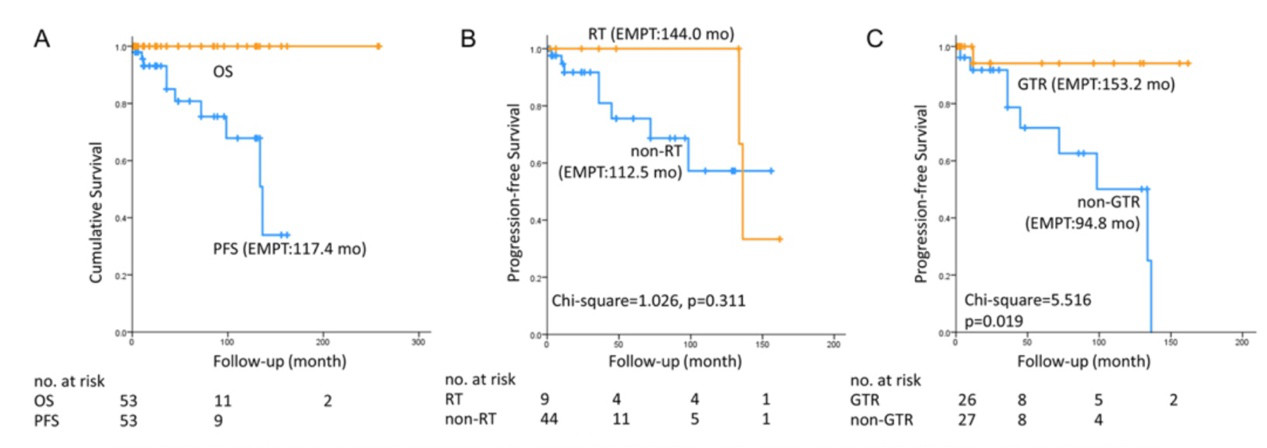

16. 原发性颅内粘液瘤的手术管理和预后因素:一项来自单中心经验的系统性回顾

Surgical management and prognostic factors for primary intracranial myxoma: a single-institute experience with a systematic review

Author: Jian-Cong Weng, Lai-Rong Song, Da Li, Liang Wang, Zhen Wu, Jun-Mei Wang, Gui-Lin Li, Wang Jia, Li-Wei Zhangand Jun-Ting Zhang

DOI: https://doi.org/10.3171/2018.6.JNS181132

原发性颅内粘液瘤(PICMs)是一种极其罕见的肿瘤,其手术管理和预后因素尚不明确。本文作者旨在通过详细地阐述其影像学特点,评价其无进展生存期(PFS)的危险因素,并且基于该中心和既往文献报道的相关病例资料,提出该疾病的诊疗策略。

有关PICMs所有病例的临床资料来自该中心所诊治的患者,以及回顾性收集了从1987年至2017年12月的英文文献报道的病例。该文作者搜索了Ovid MEDLINE, Embase, PubMed和Cochrane 等几个数据库,关键词为“粘液瘤”、“中枢神经系统”、“颅内的”、“脑内的”、“颅底”、“颅骨”或“脑”。文献的病例根据系统评价和荟萃分析优先报告的条目指南(PRISMA)进行数据处理和分析。进而对经该中心诊治和既往文献报道的相关数据进行合并,并对危险因素进行评估。

该中心的病例纳入了21名男性和9名女性患者,平均年龄为35.7±1.7岁。全切组(GTR)和非全切组(non-GTR)分别为6例(20.0%)和24例(80.0%)。该组患者的平均随访时间为86.7 ± 14.1月,其中6例(24%)患者复发,中位PFS为85.2月(36.0-136.0月),无死亡病例。从1987年至2017年收集的35例PICMs患者中,男性14名,女性21名,平均年龄为31.7± 3.2岁。GTR组和非GTR组分别为23例(65.7%)和9例(25.7%),另有3例无相关数据。该组患者的平均随访时间为25.8 ± 6.9月,其中4例(14.3%)患者复发,中位PFS为11.1月(3.0-36.0月),无死亡病例。1年、5年和10年的PFS分别为93.0%、80.6%和67.9%。多因素模型证实了GTR(HR 0.058, 95% CI 0.005–0.680, p = 0.023)是良好PFS的唯一相关因素。

PICMs这种罕见肿瘤在男性的发生率略高,GTR是良好PFS的唯一相关因素。基于统计学分析,如果条件允许,本文作者提倡GTR可作为PICM治疗的最佳治疗策略。尽管如此,术中倾向于选择姑息性切除,是为了避免损伤重要的解剖结构。PICMs在初次手术若干年后有一定复发几率,这与术中不完全切除有关。因此,密切地术后随访是必须的。上述结论还需要积攒更多的病例来证实。

图:GTR是良好PFS的唯一相关因素。

【刘畅】